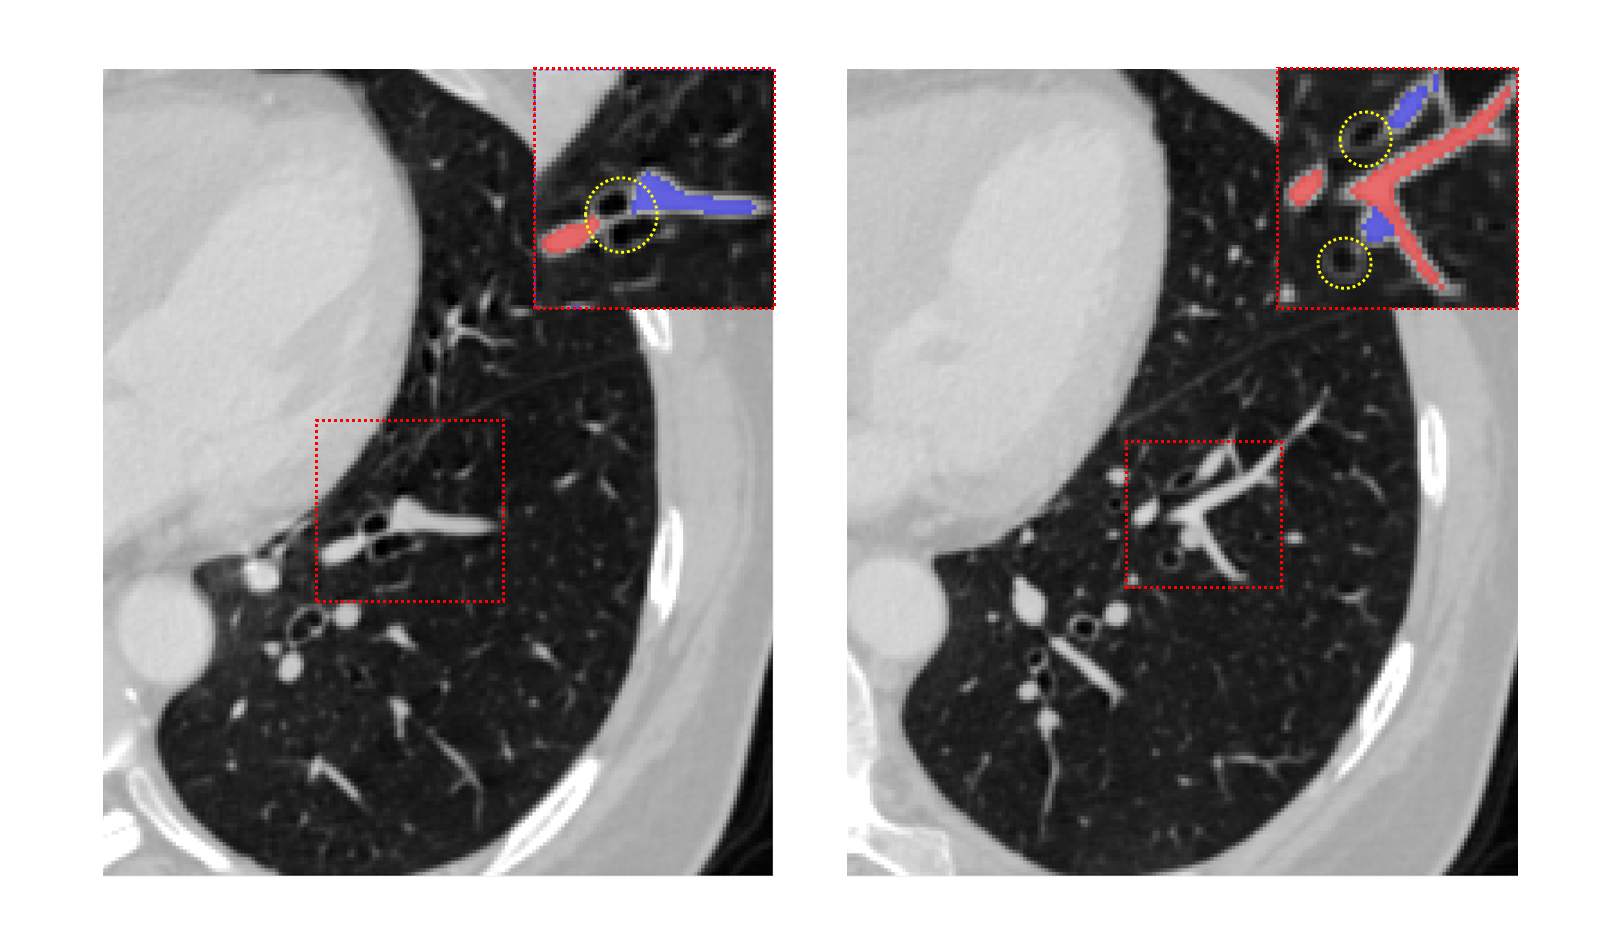

With the development of AI-assisted medical imaging diagnostic system, many scholars have tried to propose their own pulmonary A/V separation methods in the last decade, although it is very difficult. Despite the vasculature inside the lungs is very variable, some inherent anatomical properties are usually found. One property is that arteries run along the bronchi, and the veins run in between their branches. As shown in Fig. 2, the trachea with the accompanying artery is not evident when the vessels are near the hilum of the lung. As the artery moves away from the hilum, the bronchi begin to follow the artery closely. Some methods rely on the bronchi for A/V separation. Tozaki et al.[2] used information about distances between vessel segments and bronchi to separate the arteries and veins. Y.Mekada et al.[3] classified pulmonary artery and vein from X-ray CT images according to the distance from the bronchus region to the vessel segment and the distance between the nearest inter lobar to the vessel. Similarly, Buelow et al.[4] designed a method of “arterialness” to classify each extracted vessel segment. However, these methods of A/V separation depend on the quality of airway segmentation.

Finally, the topology optimizer extracts the topology subtree and topology branch refinement results by the method in Section 2.3. The results of a topology subtree and topology branch are shown in Fig. 9. Then, we use topology subtrees and topology branches for postprocessing. As shown in Table 3, the proposed topology optimizer is superior to the subtree-based and branch-based topology optimization in accuracy. Fig. 14 and 15 show the reconstructed results of different topology strategy optimizers. The results in Fig. 14 show that when the number of points on the branch is small, and the branch-based topology optimization method is prone to predict errors. This finding is mainly because the branch-based refinement strategy focuses on the relationships within the branches and ignores the topological relationships between branches. As shown in Fig. 15, topology optimization based on subtree strategy is prone to prediction errors in the case of arterial-vein intersection. This finding is mainly because the arterial/venous intersection point in the extraction process of topological subtree is easily mistaken for the bifurcation point of arterial subtrees due to the complex structure of the vascular tree, arteries and veins interweave, and finally the venous branches are classified as arterial subtrees, resulting in the classification error.

Fig. 16 shows the final separation result of our method at the intersections of the arteries and veins. The proposed topology optimizer considers the interbranch and intrabranch relationships. The extracted topological subtree is used to maintain the spatial connectivity of topological particles. The branch confidence calculated using topological branches is used to correct the topological subtree. To some extent, our method can solve the misclassification problem caused by interlaced arteries and veins.